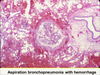

Candida bronchopneumonia

Lobar pneumonia on the left vs bronchopneumonia on right